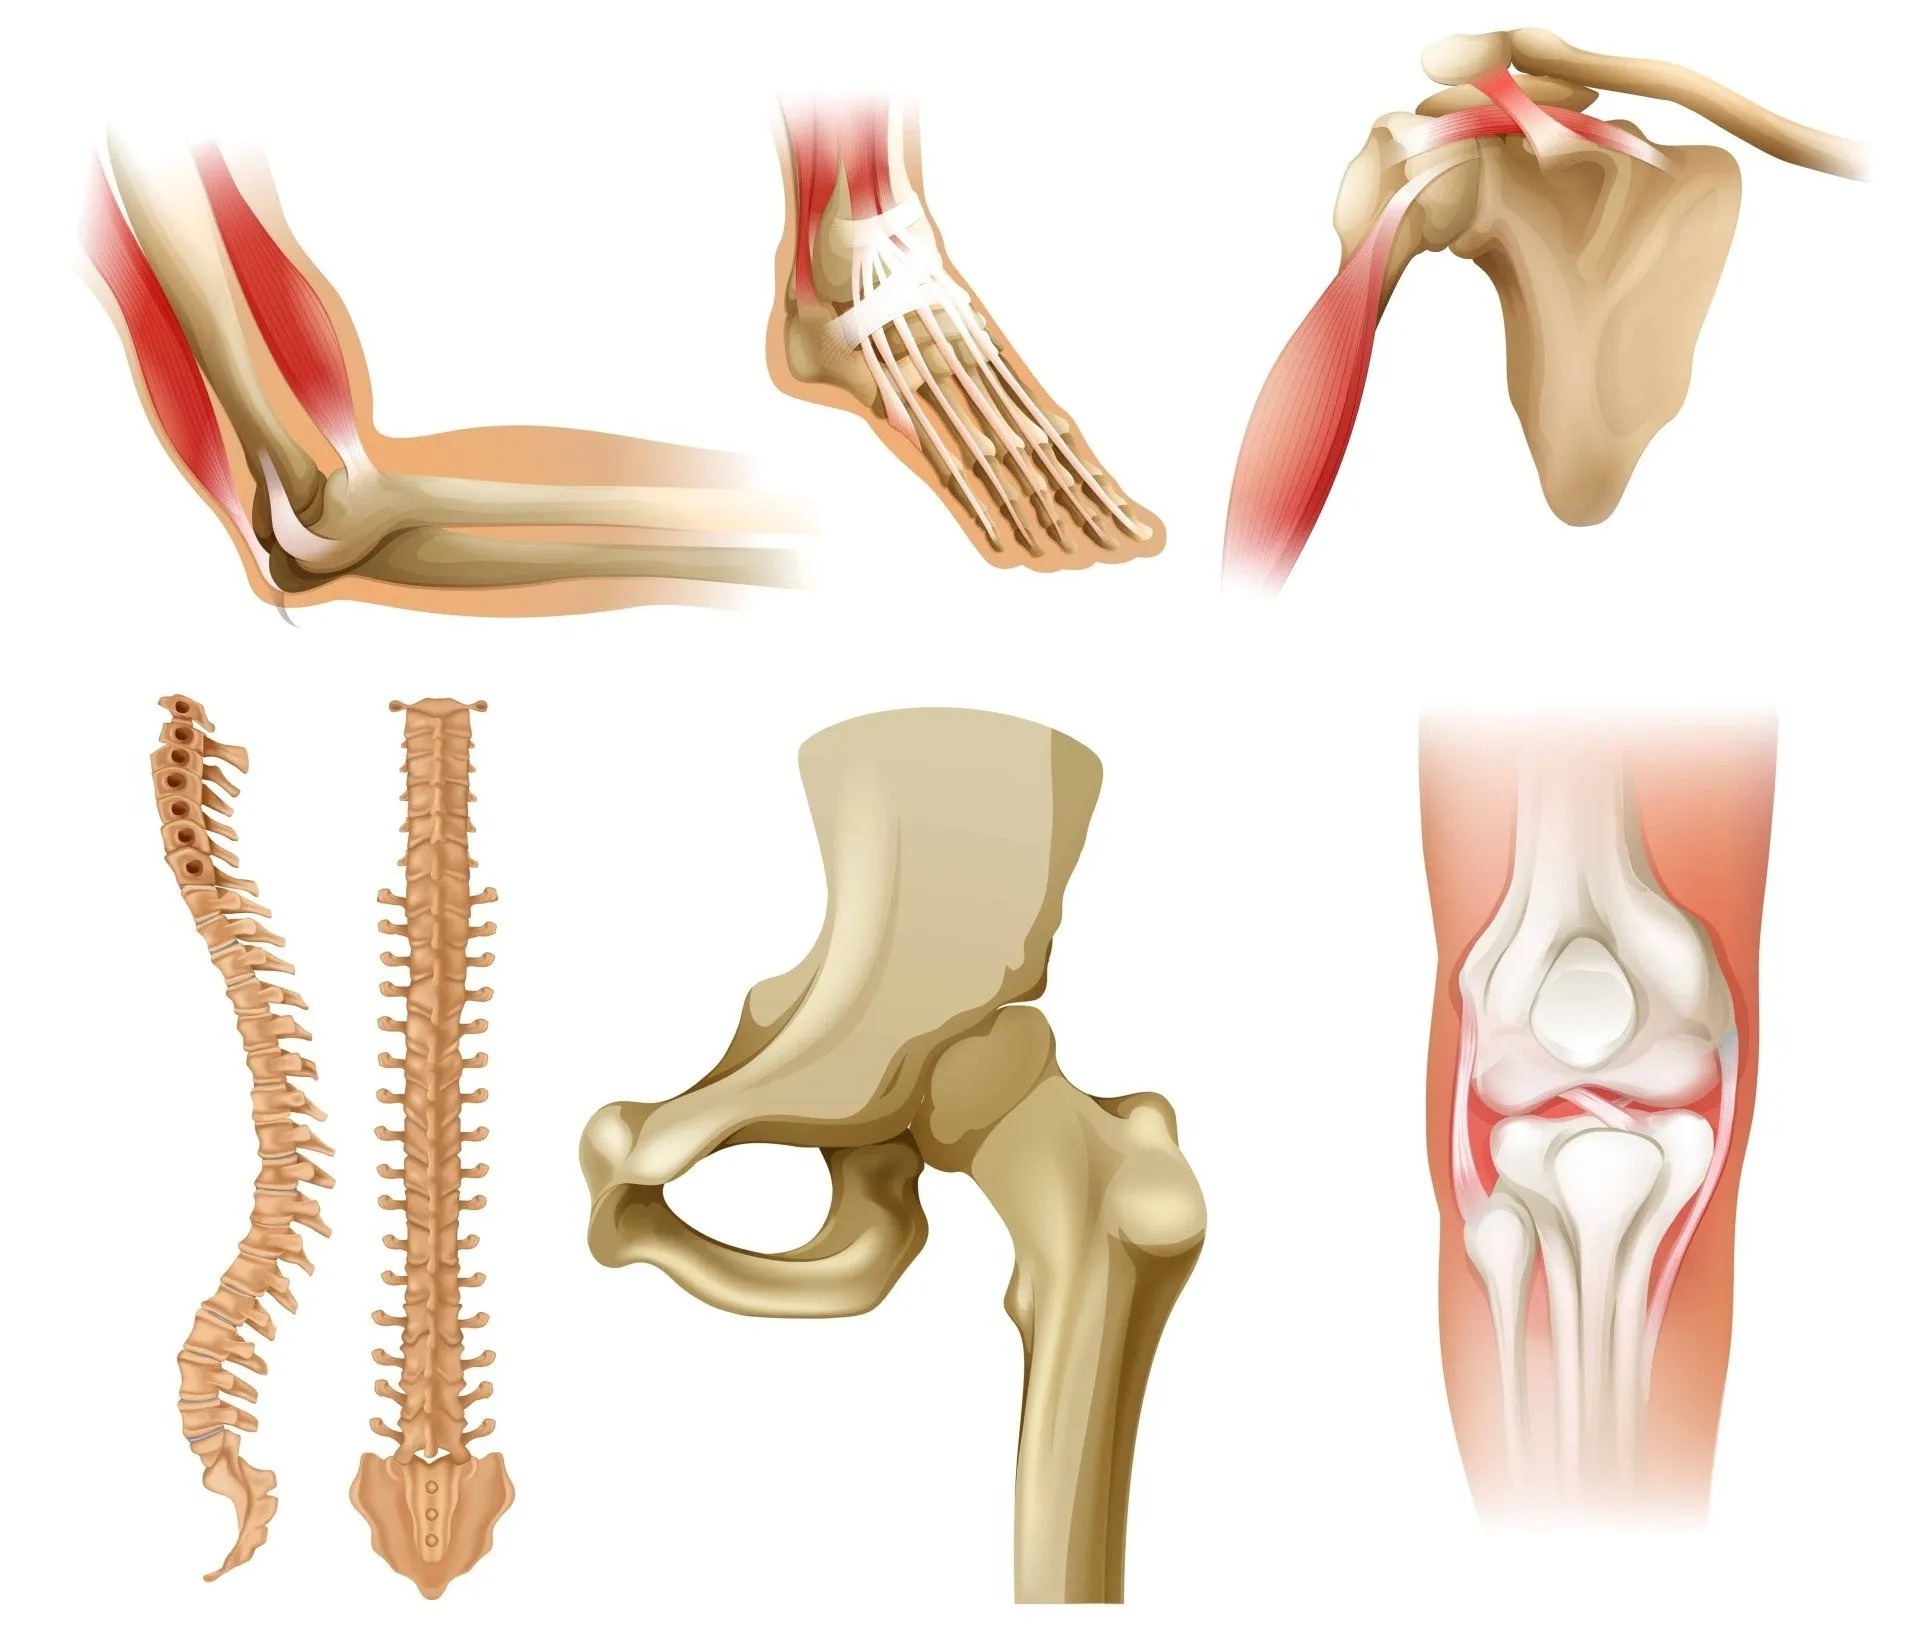

At Varah Healthcare Speciality Clinic, we understand the profound impact that joint disorders can have on daily life and overall well-being. Our specialized clinic is dedicated to providing professional and comprehensive care for joint conditions, ensuring accurate diagnosis, effective treatment, and personalized care plans to support individuals in their journey to joint health.

Osteoarthritis: Specialized care for the degeneration of joint cartilage, focusing on pain management, lifestyle adjustments, and, if necessary, joint replacement surgery.

Rheumatoid Arthritis: Comprehensive management for this autoimmune condition, including medication, physical therapy, and joint protection strategies.

Gout: Expert evaluation and treatment for gout, addressing the underlying cause and managing symptoms.

Joint Infections: Specialized care for infections affecting the joints, including antibiotic therapy and, in severe cases, surgical intervention.

Joint Injuries: Focused treatment for traumatic injuries to the joints, including fractures, dislocations, and ligament injuries.

At Varah Healthcare Speciality Clinic, we provide comprehensive care for joint disorders, recognizing the importance of addressing the individual needs of each patient. Our approach involves not only managing the specific joint disorder but also supporting overall musculoskeletal health and quality of life.